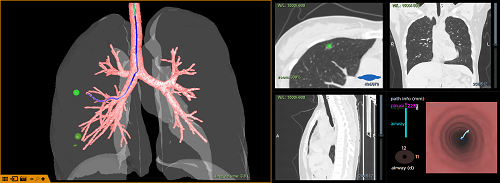

图一:术前引用导航系统规划路径(右中叶结节)

图二:术前引用导航系统规划路径(右下叶结节)

此次手术前,通过导航系统对患者CT进行三维重建规划和评估分析,患者病灶分别位于右肺中叶外侧段、右肺下叶前基底段,大小分别约为10mm*2mm、8mm*2mm,均为磨玻璃结节且邻近胸膜,常规定位手段无法准确定位。为精准定位结节,马宇超博士利用导航系统沿自然腔道染色定位肺结节,为实现精准切除创造条件,既最大程度保留了健康肺组织,又确保彻底切除病变组织。